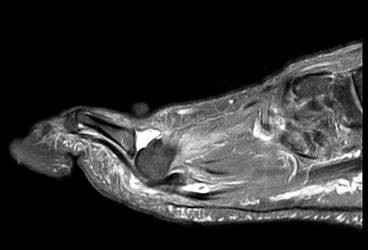

Die Überbelastung des Metatarsale II und III im distalen Bereich äußert sich in Druckschmerzen und Schwielenbildung plantar unter den Metatarsale II und III Köpfen (Abb. 1). Auch degenerative Veränderungen der plantaren Kapsel und der plantaren Platte der Metatarsophalangealgelenke treten auf, was zu einer Insuffizienz der Grundgelenke mit Subluxation oder Luxation der Kleinzehen führt (Abb. 2 und 3).